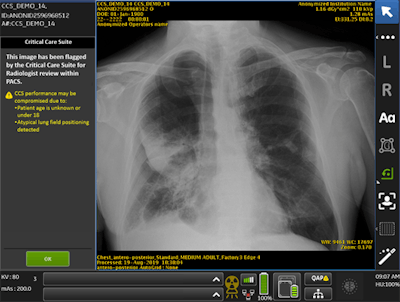

GE selected the medical center in November 2019 as the first hospital in the U.S. to study Optima XR240amx with Critical Care Suite, an AI-based application designed to identify urgent cases such as pneumothorax and flag these exams for urgent review, according to the institution. The Cleveland researchers completed the evaluation phase of Critical Care Suite in December, noting the technology flagged seven to 15 collapsed lungs per day.

The system has now been placed into daily clinical use, and principal investigator Dr. Amit Gupta said in a press release that the technology has helped improve workflow and patient care.